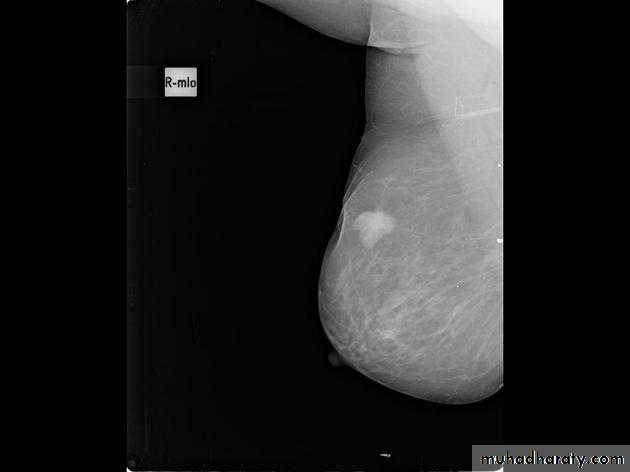

The mediolateral oblique (MLO) view is one of standard mammographic views. It is the most important projection as it allows to depict most breast tissue.